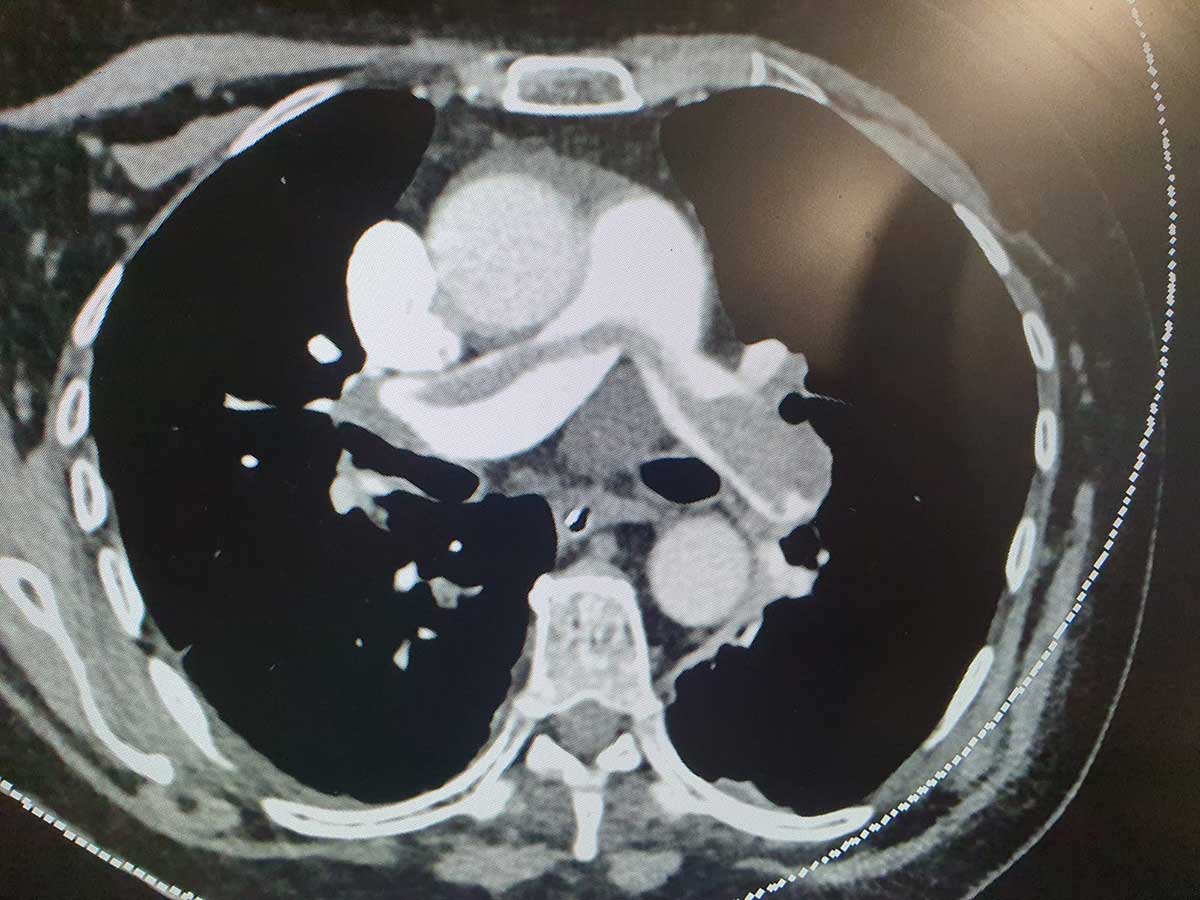

ביצוע השאיבה. צילום: שערי צדק

במרכז הרפואי שערי צדק בוצע לראשונה טיפול חדשני במכשיר פורץ דרך זה, לשאיבת קרישי דם מעורקי הריאה עקב תסחיף ריאתי. הטיפול החדשני הציל את חייה של מטופלת בת 76, שסבלה ממחלה פתאומית של דימום יתר וקרישי דם מסוכנים. המטופלת, תושבת ירושלים, הגיעה ליחידה לטיפול נמרץ לב במרכז הרפואי שערי צדק, במצב של תסחיף ריאתי גדול ומסכן חיים, עם לחץ דם גבולי וקריסה של חדר ימין. לאחר שבוצע CT ללב אובחן התסחיף הריאתי. ד"ר אלעד אשר, מנהל היחידה לטיפול נמרץ לב בשערי צדק, הוזעק למקום ולאחר בדיקה מקיפה, הוחלט לבצע את שאיבת קרישי הדם מהלב.